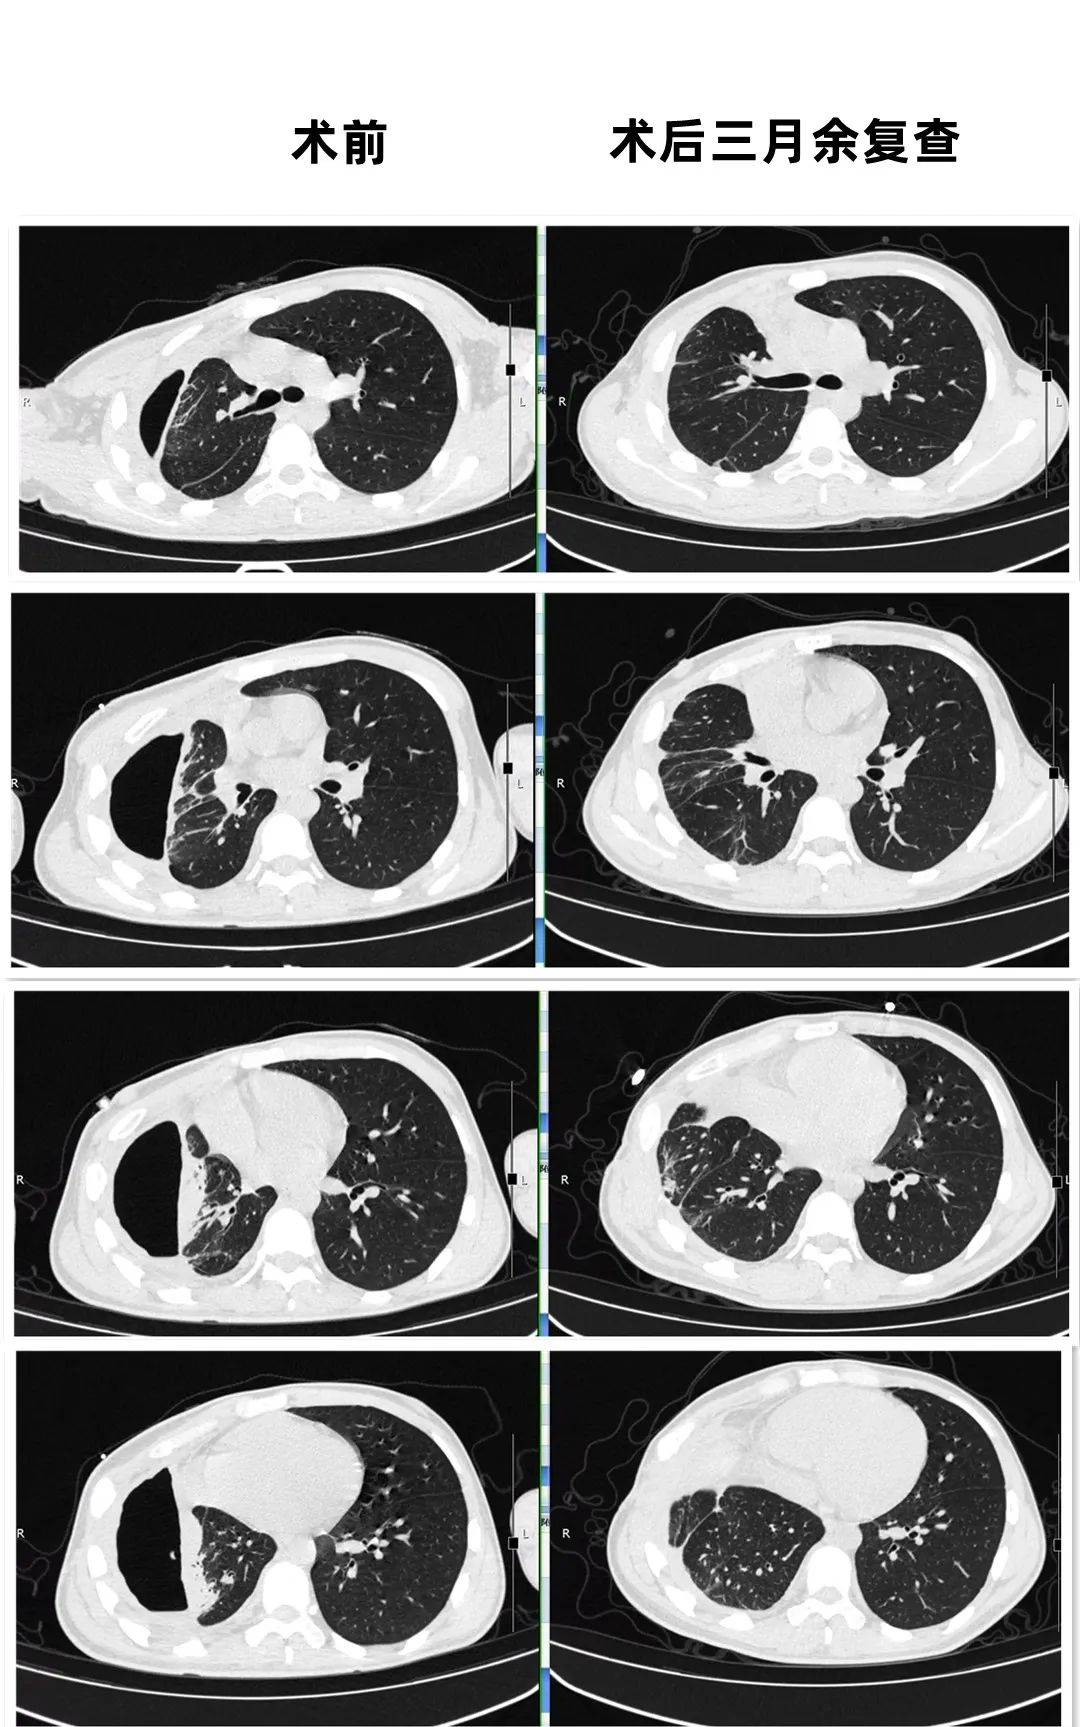

一个肺脓肿患者,差点被误诊为肺癌 这个病人50岁,咳嗽,咳痰四五天了

ct 影像显示肺部存在一个大厚壁空洞,大小 62*44mm,需要鉴别脓肿伴